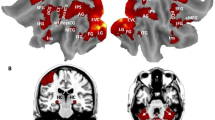

Calculating prodigies are individuals who are exceptional at quickly and accurately solving complex mental calculations. With positron emission tomography (PET), we investigated the neural bases of the cognitive abilities of an expert calculator and a group of non-experts, contrasting complex mental calculation to memory retrieval of arithmetic facts. We demonstrated that calculation expertise was not due to increased activity of processes that exist in non-experts; rather, the expert and the non-experts used different brain areas for calculation. We found that the expert could switch between short-term effort-requiring storage strategies and highly efficient episodic memory encoding and retrieval, a process that was sustained by right prefrontal and medial temporal areas.

Pesenti, M., Zago, L., Crivello, F. et al. Mental calculation in a prodigy is sustained by right prefrontal and medial temporal areas. Nat Neurosci 4, 103–107 (2001). https://doi.org/10.1038/82831